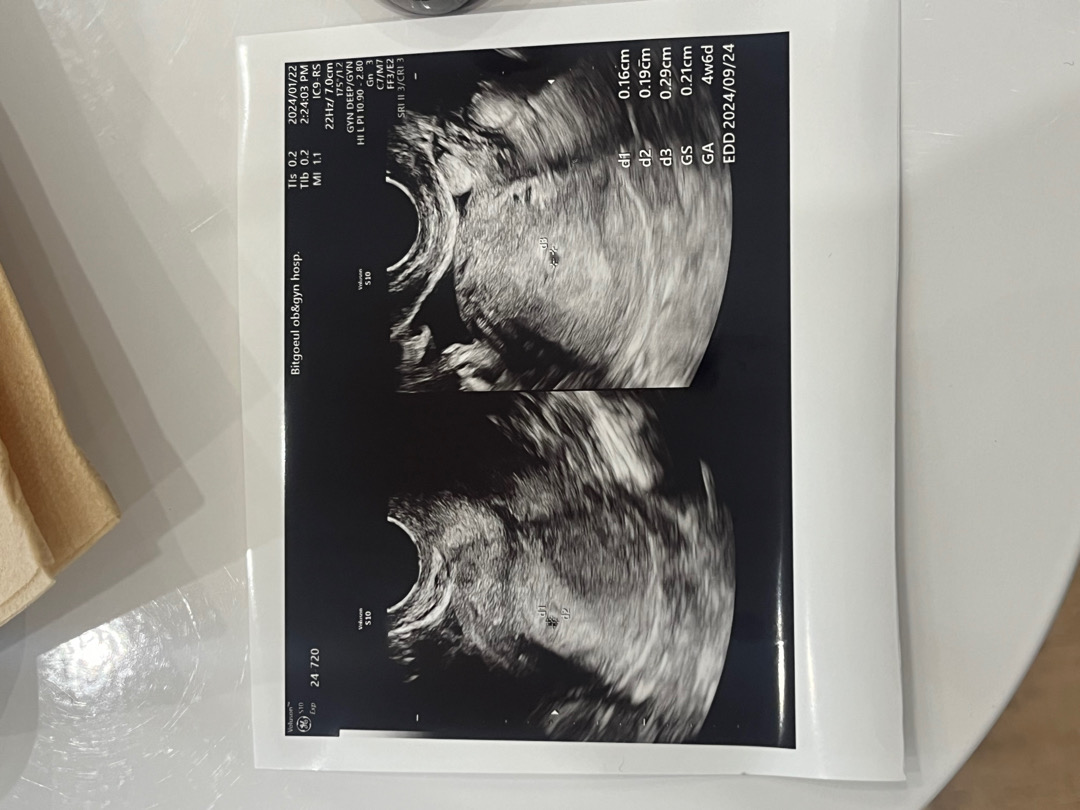

마지막생리가 12/15이고 1/22일에 병원가서 4-5주 아기집 0.2cm 확인하고왔어요~! 2주 뒤인 2/6일에 방문해서 심소 들어보자고 하시던데 그날이 평일이라 3일 당겨서 2/3토요일에 병원가볼까하거든요! 이때에도 심소 들어볼수있을까요..??

저랑 막생 똑같아요! 1/20에 아기집 0.16cm 확인했고 내일 다시 방문 하기로 했어요 너무 궁금..